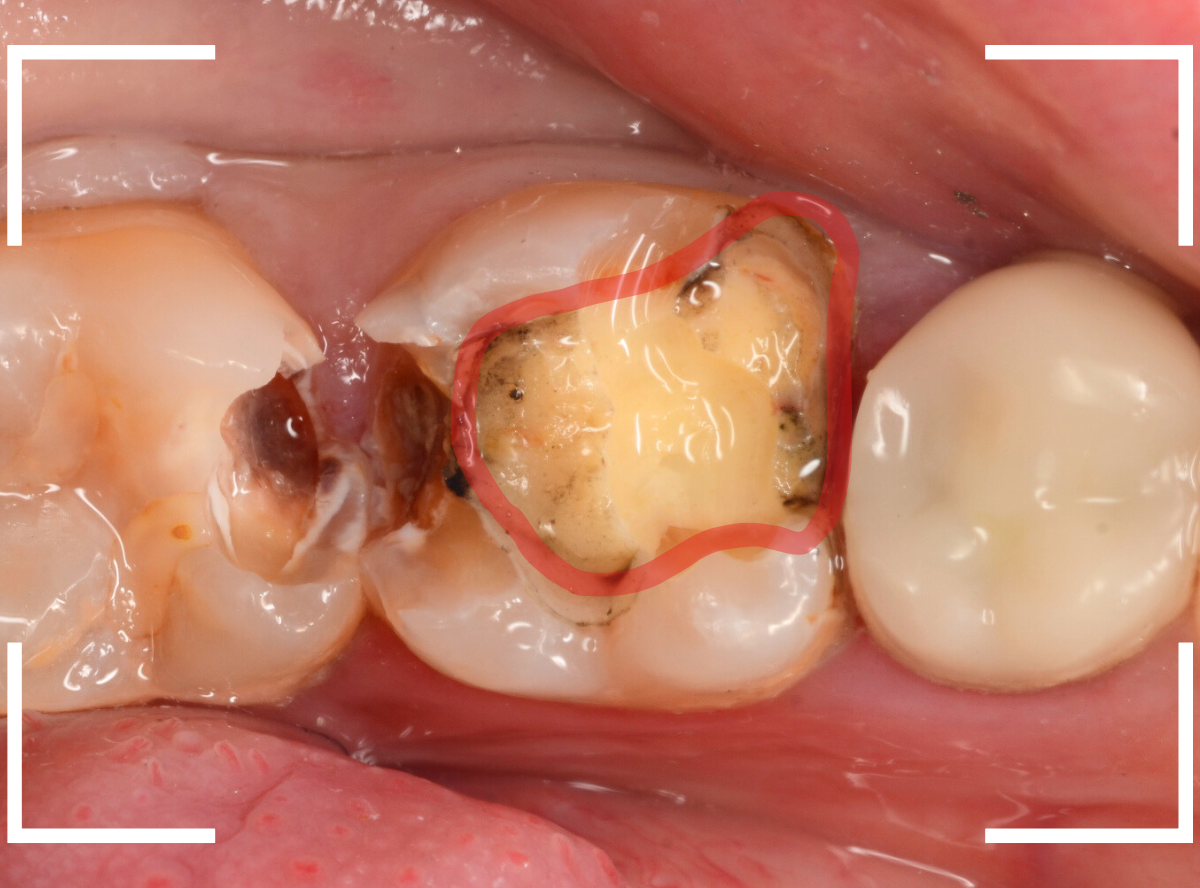

レントゲン写真で虫歯の状況を確認すると、赤い線のように虫歯になってるであろう事が予測できます。

金属を外して、ある程度虫歯を除去したところです。

金属の下にしいてあるセメントも劣化してますので、中が虫歯になっていないかどうか、セメントも除去して調べます。

セメントまで除去したところです。

神経まで近い、かなり深い虫歯になっているのがわかります。